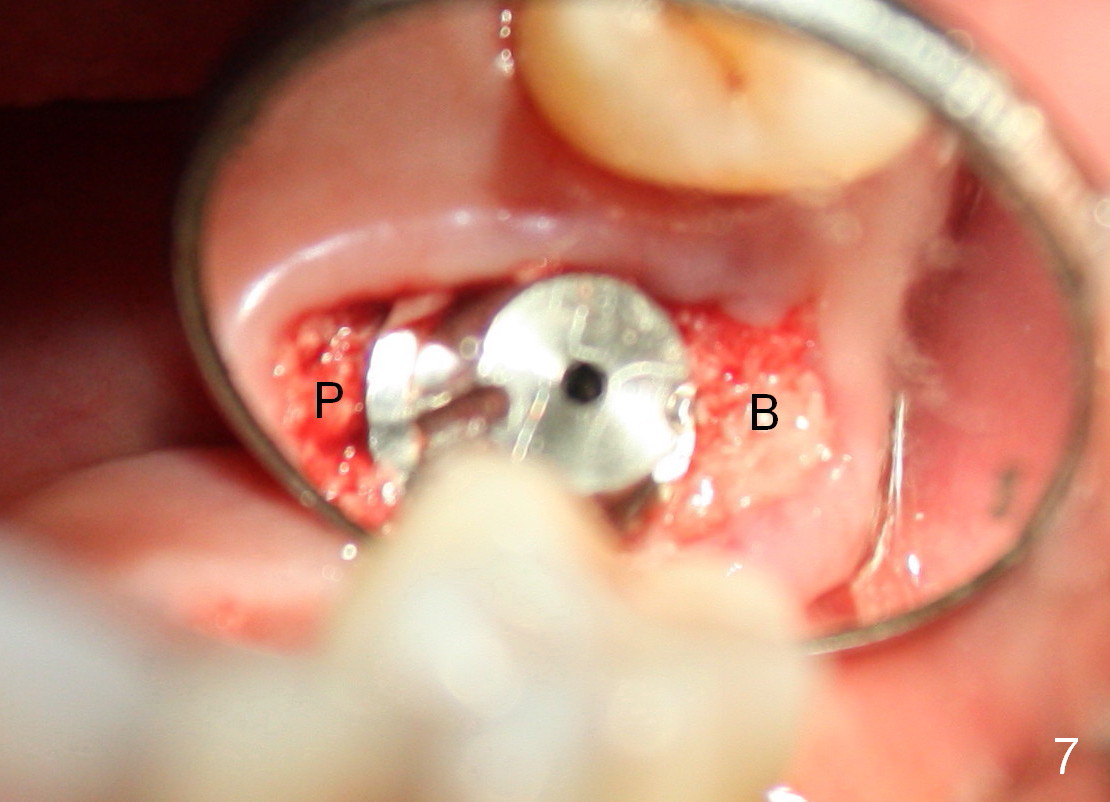

The large implant obliterates the socket mesiodistally (Fig.7); the buccal (B) and palatal (P) gaps are filled with bone graft, which is held in place by an immediate provisional.